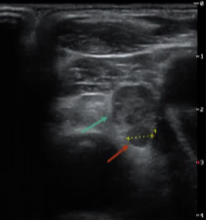

获得书面知情同意,在局部麻醉和和静脉注射镇静药物。颈部伸展的体位完全暴露并消毒。超声引导下,穿刺部位注射局麻,使用带Icm工作尖端的18号射频电极和移动射击技术消融甲状旁腺。射频功率为35W,避免热损伤累及相邻结构为。治疗时甲状旁腺为高回声。最后按压颈部止血。没有观察到并发症,但在手术过程中疼痛是可以忍受的。术后6个月对患者进行上述异常血清的实验室检查,结果正常。 三发甲状旁腺功能亢进